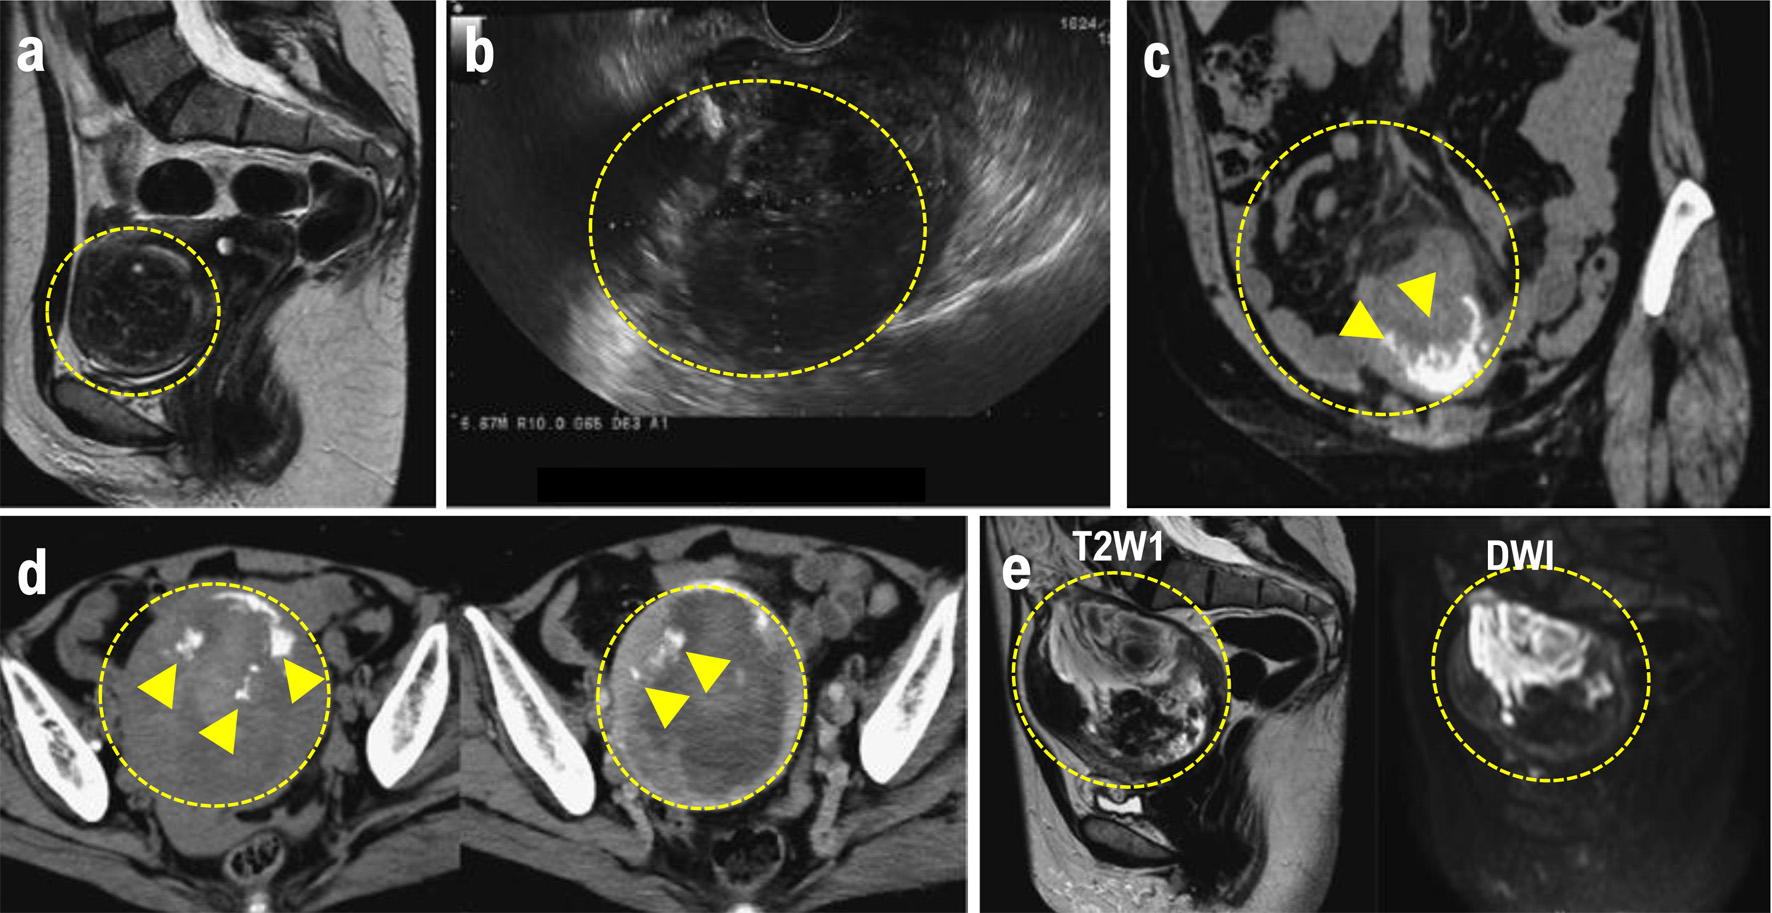

Figure 1. (a) MRI performed at the initial consultation. The mass exhibited a clearly demarcated low signal intensity on T2W1 and was diagnosed as a uterine fibroid. (b) Transvaginal ultrasound after lower gastrointestinal endoscopy revealed a 90 × 69 mm mass in the uterine body, with a heterogeneous interior and irregular margins. (c) Plain CT. Increased density was observed in the mesenteric fat tissue surrounding the mass. A mass with marginal calcification was found on the anterior wall of the uterine body, protruding cephalad. (d) Comparison of the initial CT (left) with a CT performed 8 days later for preoperative evaluation (right). The uterine mass had shrunk from 10 × 11 cm (left panel) to 10 × 9.5 cm (right panel), and the absorption value of the internal high-density area had decreased, suggesting absorption of the hematoma. (e) MRI for further investigation of suspected uterine sarcoma. The mass showed moderate signal intensity on T2W1 and high signal intensity on DWI, and heterogeneous signals were present within it, suggesting hemorrhage and necrosis. The mass is indicated by the yellow dotted circle. Heterologous components including osteosarcoma and chondrosarcoma are indicated by the white arrowheads. CT: computed tomography; MRI: magnetic resonance imaging.

At 48 years of age, the patient was diagnosed with anemia (Hb 8.8 g/dL). As a result, she was referred to our gynecological clinic for further evaluation to determine the presence of a gynecological disease. Transvaginal ultrasonography revealed a large mass (48 × 50 mm) compressing the lining of the anterior uterine wall. Based on the contrast-enhanced magnetic resonance imaging (MRI) findings, the mass was diagnosed as a uterine leiomyoma (Fig. 1a). However, because the patient preferred monitoring until menopause, we prescribed iron supplements to treat the anemia and continued tumor follow-up. The tumor did not exhibit any signs of enlargement. At 56 years of age, however, she developed lower abdominal pain after undergoing an endoscopic examination of the lower gastrointestinal tract. Blood tests revealed an elevated C-reactive protein (CRP) level (8.49 mg/dL). We suspected peritonitis due to delayed perforation and performed contrast-enhanced computed tomography (CT). Imaging revealed increased adipose tissue density in the mesenteric lining around the uterus and ascites.

The findings resulting from a physical examination were as follows: blood pressure, 135/72 mm Hg; pulse, 64 beats/min; mild abdominal tenderness. Pelvic examination revealed a small amount of white vaginal discharge, erosions in the uterine vaginal region, a first-sized and mildly tender uterine body, and a non-palpable adnexa. Transvaginal ultrasonography revealed a 90 × 69 mm heterogeneous mass with irregular margins on the uterine body (Fig. 1b). Blood tests revealed no abnormalities except for an elevated platelet count of 500,000/µL. The liver and renal function test results were normal. The serum lactate dehydrogenase (LDH) and total protein (TP) levels were elevated to 401 U/L and 8.2 g/dL, respectively. The fibrinogen level was 604 mg/dL, indicating coagulation abnormalities. The CRP level was 0.37 mg/mL, slightly above the normal range. The tumor marker levels were within normal limits: CEA 1.8 ng/mL, CA19-9 9 U/mL, and CA125 18 U/mL. Endoscopy of the lower gastrointestinal tract showed no abnormal findings. Truncal CT (Fig. 1c) revealed a 10 × 11 cm mass with marginal calcification on the anterior uterine wall and cranial protrusions of the uterus. A pale, low-density area suggestive of a hemorrhage was observed within the mass, and a small amount of pelvic fluid was present, indicative of the presence of blood. The increased adipose tissue density surrounding the mass was suggestive of a possible rupture.

A contrast-enhanced CT performed for preoperative evaluation 8 days after the initial scan showed that the uterine mass had decreased to 9.5 × 9.5 cm and the bloody ascites had resolved (Fig. 1d). The fat density surrounding the cranial protrusion of the uterus decreased, and the wall in that region thinned. The low-density background area within the mass became less prominent, indicative of a reduction in bloody fluid. No lymph node enlargement or distant metastasis was observed. Pelvic contrast-enhanced MRI (Fig. 1e) showed a 10-cm mass located within the muscle layer of the anterior uterine wall. T2W1 demonstrated moderate signal intensity within the mass and DWI demonstrated high signal intensity. Heterogeneous internal signals suggestive of hemorrhage and necrosis were observed. T2W1 also showed signal imaging, which showed a low signal area on the ventral side of the mass. CT revealed areas of calcification, and contrast-enhanced MRI confirmed that both ovaries were normal. Based on the rapid tumor growth accompanied by bleeding, necrosis, rupture, and elevated LDH levels, rupture of the uterine leiomyosarcoma was suspected. The preoperative stage corresponded to stage IB disease.